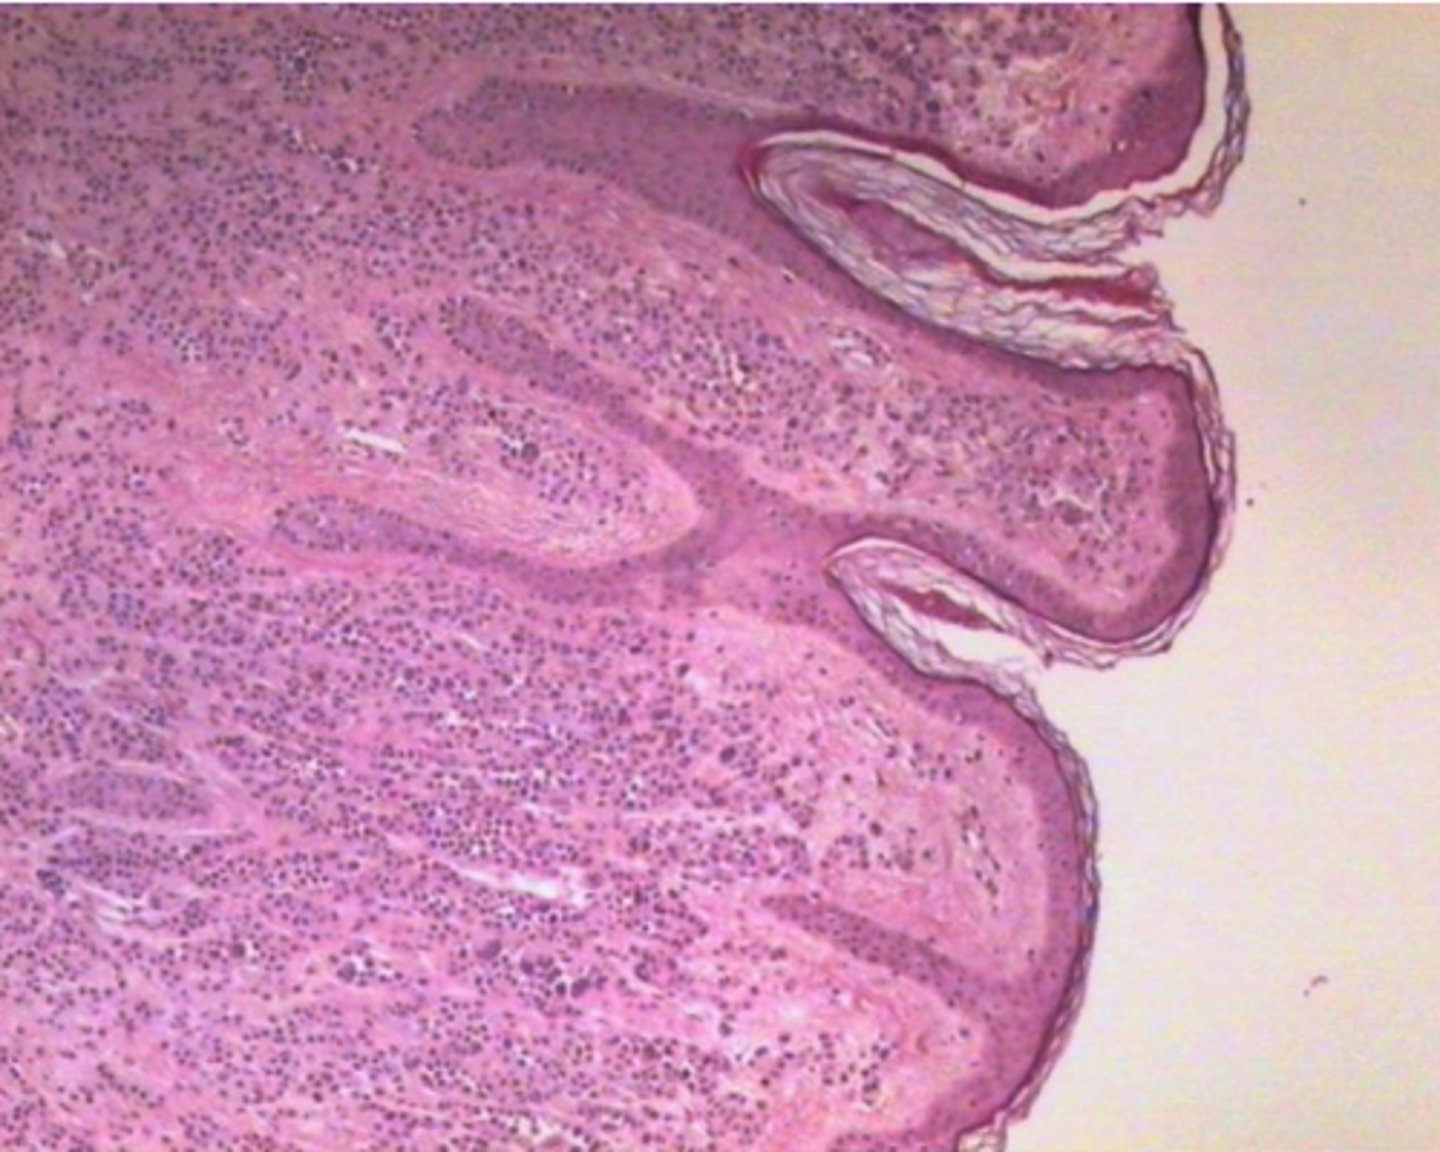

Intradermāls naevus

Intradermāls naevus ar pigmentu